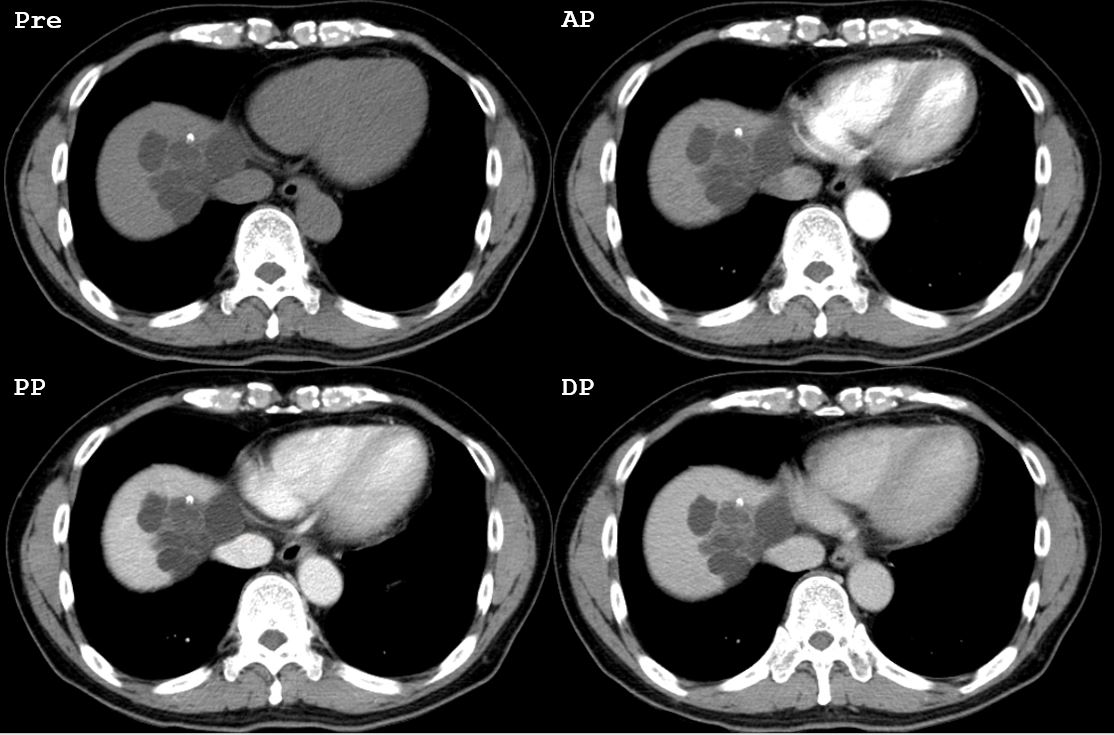

Case

No.726

F / 28

liver nodule detected on a screening test

ABDOMEN

ºÐ´ç¼¿ï´ëÇб³º´¿ø ±Çöȣ

CASE 1

1

2026-04-11